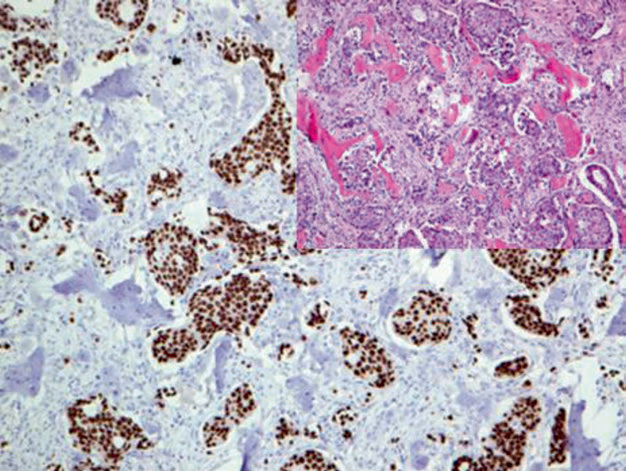

Positive expression pattern: Nucleus

Recommended positive control tissue: Normal breast tissue

GATA-3 is involved in the regulation of breast luminal epithelial proliferation and differentiation, as well as in the differentiation of T lymphocytes and skin appendages. In clinical practice, GATA-3 is widely used in the diagnosis and differential diagnosis of primary and metastatic breast cancer and transitional cell carcinoma. Up to 90% of breast cancers express GATA-3, but the positivity rate is lowest in triple-negative breast cancer, and also low in metaplastic breast cancer and sarcomatoid breast cancer. In male breast cancer, the GATA-3 positivity rate is only one-third. Strong positive expression of GATA-3 in breast cancer is also accompanied by ER expression; high expression of GATA-3 generally indicates a better prognosis.

Figure 3. Breast invasive ductal carcinoma, bone metastasis; immunohistochemistry shows strong positive nuclear expression of GATA-3 in tumor cells.

As mentioned earlier, GATA-3 can also be applied to the diagnosis and differential diagnosis of primary and metastatic transitional cell carcinoma, which will be detailed later in this series of articles. However, besides these, many other tissues and tumors express GATA-3, and caution should be exercised in interpretation to avoid pitfalls. Specifically, mesothelioma, squamous cell carcinomas of various organs, pancreatic ductal adenocarcinoma, skin appendage tumors, and various benign and malignant salivary gland tumors (such as salivary duct carcinoma, acinic cell carcinoma, adenoid cystic carcinoma, epithelial-myoepithelial carcinoma) show varying degrees of GATA-3 expression. It has also been reported that a few endometrial cancers express GATA-3. GATA-3 expression is also characteristic of T lymphocytes and peripheral T-cell lymphoma. Notably, reactive mesothelium also expresses GATA-3. Due to these issues, the specificity of GATA-3 should be considered when used for breast tumor and urothelial tumor diagnosis.